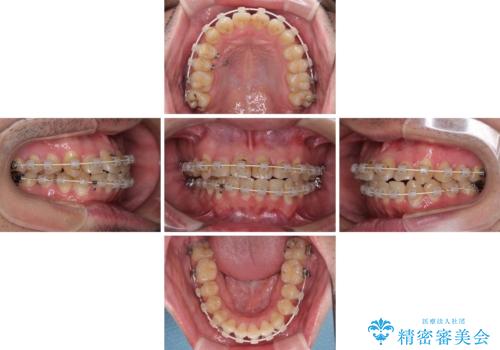

- 審美装置

- 治療期間

- 2年

クロスバイトは、治療の過程で咬み合わせが大きく変化する期間があり、食事が取りにくくなってしまいます。

また、装置が対合歯と咬み合ってしまい、頻繁に脱落するなど、色々と面倒なことがあり、治療がスムーズに進まないことがあります。